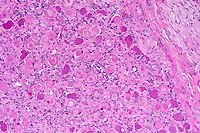

- Case 9-3 . Kidney. The tumor capsule is infiltrated

by nests, cords, and tubule forming pleomorphic polygonal cells.

There are scattered foci of necrosis and occasional mitoses.

- Case 9-3. Kidney. A bright pink amorphous to hyaline

material separates tumor cells in many areas. Generally these

areas lack silver staining (black), indicating that this material

is not collagen or basement membrane.